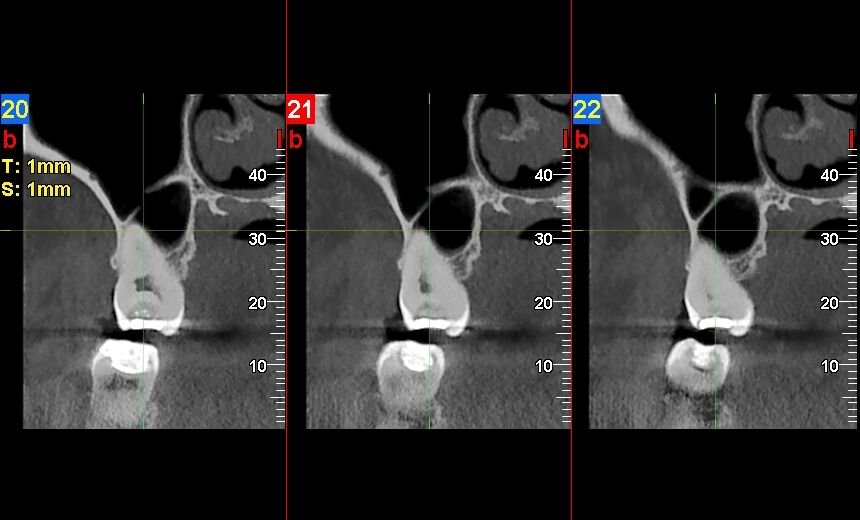

- El Tac Cervical se realiza mediante un escáner que toma imágenes detalladas de la columna cervical, permitiendo identificar lesiones con precisión.

A través de un TAC cervical se pueden detectar diversas condiciones médicas que afectan la columna vertebral y las estructuras circundantes. Entre las patologías más comunes se encuentran las hernias discales, que pueden comprimir nervios y causar dolor o debilidad en las extremidades. También se pueden identificar fracturas vertebrales resultantes de traumatismos o caídas.

Además, el TAC cervical permite visualizar tumores o masas anormales en la región cervical, así como signos de enfermedades degenerativas como la osteoartritis. Esta capacidad para detectar una amplia gama de condiciones hace que el TAC sea una herramienta invaluable en el diagnóstico y tratamiento médico.

A través de un Tac Cervical se pueden detectar fracturas, lesiones en los tejidos blandos, hernias discales, estenosis espinal, tumores, infecciones y otras afecciones que afectan la columna cervical.